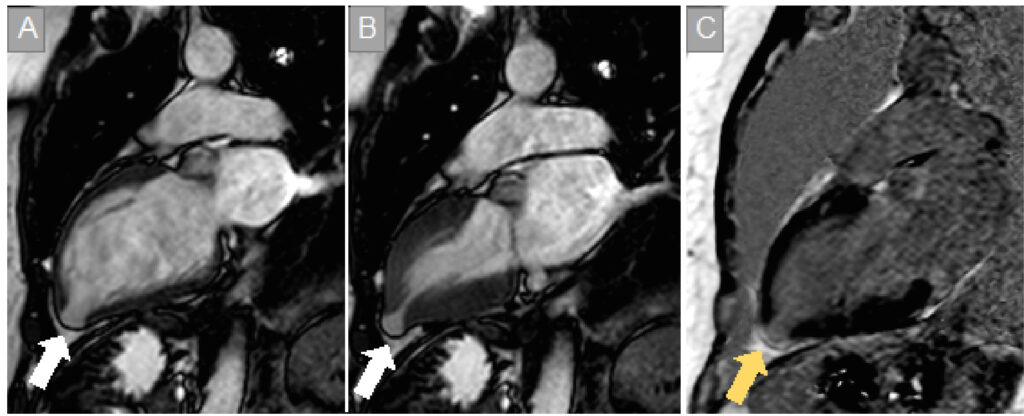

Myocardial Involvement in Chagas Disease: From the Perspective of Cardiovascular Magnetic Ressonance Assessment

Chagas disease represents an important public health problem, especially in endemic countries in Latin America. Chronic cardiomyopathy is its most frequent clinical presentation. Myocardial involvement has a multifactorial pathogenesis and can lead to heart failure, thromboembolic events, arrhythmias, and sudden death. In this context, cardiovascular magnetic resonance imaging (CMR) is an excellent noninvasive method for investigating myocardial damage and understanding the mechanisms and consequences of these injuries. CMR has high spatial resolution and tissue characterization capacity, enabling a highly reliable morphofunctional analysis and the identification of risk markers for adverse events in patients with Chagas disease. This exam is very useful for the diagnosis and follow-up of these patients in the routine clinical setting.